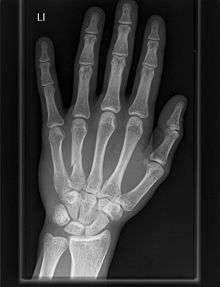

The carpometacarpal (CMC) joints are five joints in the wrist that articulate the distal row of carpal bones and the proximal bases of the five metacarpal bones.

Fingers

- The second metacarpal articulates primarily with the trapezoid and secondarily with the trapezium and capitate.

- The third metacarpal articulates primarily with the capitate,

- The fourth metacarpal articulates with the capitate and hamate.

- The fifth metacarpal articulates with the hamate.